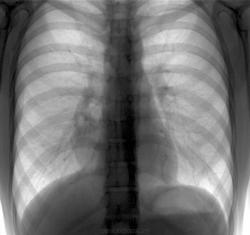

Может быть киста перикарда?

Помогите разобраться с патологией, скопия ситуацию не прояснила. Но что увидели на скопии пульсацию смещение при глубоком дыхании.

Согласен, может быть передаточная. Но вместе с смещаемоутью при глубоком дыхании это тоже информация. И помимо наличия может быть отсутствие таковой.

Липома кардиодиафрагмального угла?

У столь юных (по прямой рентгенограмме), липома, в данном месте, не часто, а вот, у пожилих - это типичное место для липомы - "Олимп" липом. Правда, не все признают этот термин "липома - медиастинальная липом, утверждают, что термин не корректен и "сие" надо называть жировой "подушкой". По поводу корректности можнобыло-бы поспорить - "что делает "подушка", пусть и жировая в грудной полости"?

На скопиии опр. пульсация ,никаких дополнительных образований

Зазвать в кабинет УЗИ и ткнуть секторным или конвексным датчиком в правый кардио-диафрагмальный угол.

Это и бронхо-энтерогенной кистой может быть: нижний контур образования образует острый угол, на боковом снимке возможно проецируется позади сердечной тени.

Девушка тогда обследоваться отказалась, обьясняя хорошим самочувствием, через год пришла снова. Самоизлечение?